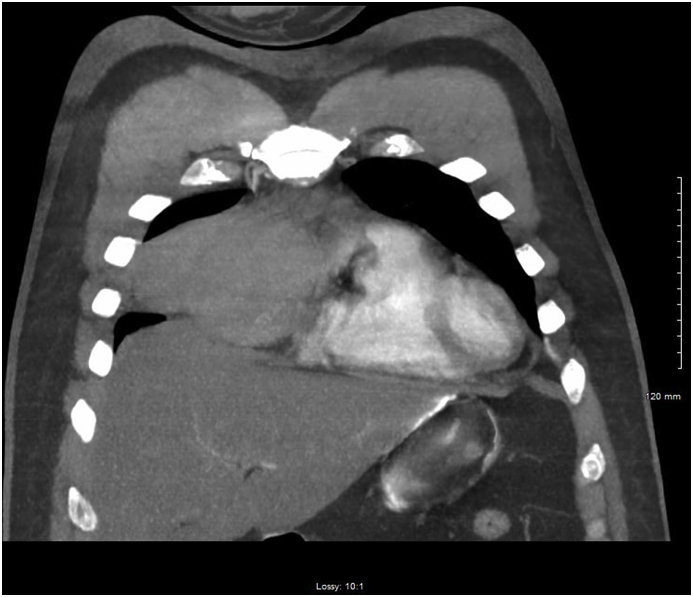

Fig. 3.

Computerized tomography of the chest showing right hemithorax.

Fig. 4.

Computerized tomography of the chest demonstrating the tumor with mass effect on the superior vena cava and the right atrium.

At the time of clinical deterioration vital signs were as following-temperature was 98.3 °F, HR 120 BPM, BP 154/93 mm Hg, respiratory rate 26 breaths per minute and SpO2 on 11 L per nasal cannula was 92%. At that time, he appeared to be in respiratory distress. There was no JVD. Chest examination revealed decreased breath sounds on the right; there was no crackles, rales or wheezing. He was tachycardic, and there was no murmurs, rubs or gallops. EKG showed new onset RBBB. There was a concern for pulmonary embolism and subsequently he underwent CT of the chest which showed a mass along the right anterior mediastinum, resulting in mass effect upon the distal right superior vena cava, and right atrium with associated right-sided hemothorax (Fig. 1, Fig. 2, Fig. 3, Fig. 4). CBC was significant for hemoglobin 13.5 g/dl. A right-sided chest tube was inserted which immediately drained one liter of blood. Over the next 24 hours, there was a minimal drainage through the chest tube. Patient subsequently had MRI of the chest which identified 8.8 cm low T1 and low T2 signal mass closely related to the right pericardium, containing multiple foci of cystic fluid without enhancement. AFP, B- HCG and TSH were within normal limits (see Fig. 5, Fig. 6, Fig. 7, Fig. 8).